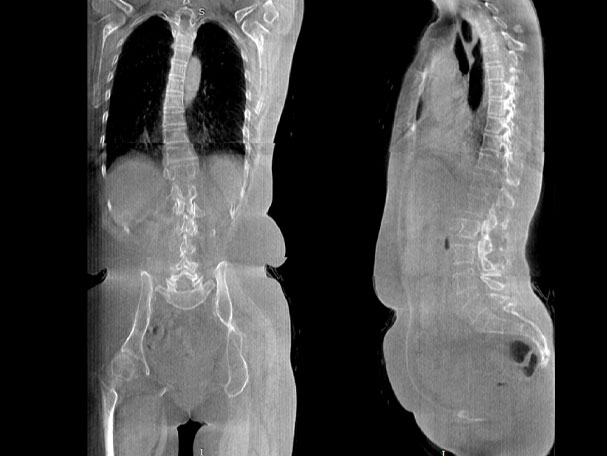

• 全身姿態評估

WR-3D能提供一種負重位狀態下全身的姿態和三維空間任一平面平衡評估,使全脊柱術后評價更客觀、真實 。通過各種臨床參數包括骨盆、脊柱參數評價骨盆、脊柱平衡,避免由于髖膝屈曲造成的代償性脊柱失衡的發生,WR-3D提供了三維空間任一平面平衡評估測量方法,可以更加定量地評估手術效果 。